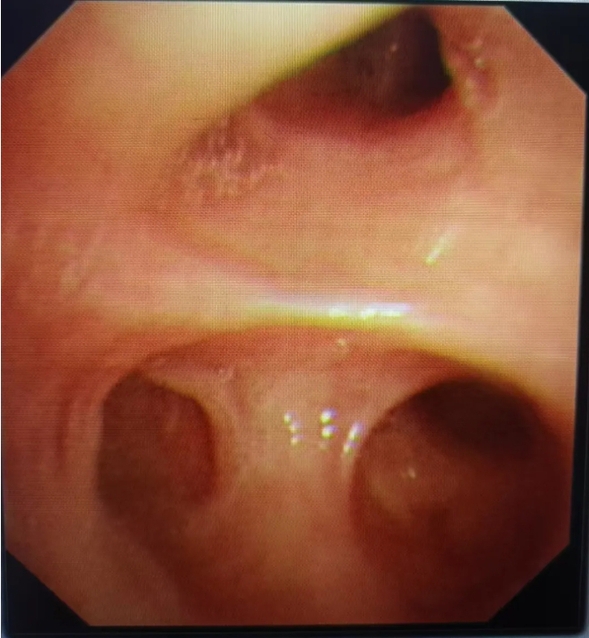

纤维支气管镜下影像

为了明确肺部感染的病因,急需纤维支气管镜的辅助,纤维支气管镜是呼吸感染性疾病医生的好帮手。纤维支气管镜经口或鼻置入下呼吸道,进入气管或支气管以及更远端,医生通过显示屏成像或直接通过目镜,可以清晰的观察气管及支气管的病变。对于严重肺部感染的患者,可以行支气管肺泡灌洗,清除气道内的痰,栓塞,痰栓,以及纤维支气管镜灌洗过后可降低气道内的有害因子,增加气道清洁性,减少全身抗生素的使用。

我院感染科负责人张维彬与呼吸与危重症医学科一病区医生聂焱对患者进行了查体,结合资料,考虑在这种情况下,如果继续保守治疗,有可能导致患者病程时间长,感染迁延不愈。为了最大程度减少患者的痛苦,我院感染科医疗团队决定给予患者支气管镜下灌洗治疗术。在麻醉科和腔镜室等科室的协助下,我院感染科成功开展了首例纤维支气管镜检查、肺泡灌洗治疗技术,目前患者恢复疗效较好。